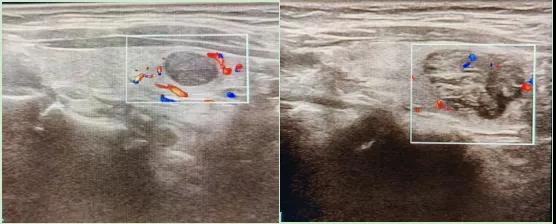

二、彩超如何“揪出”甲狀腺瘤?

彩超是一種無創、無輻射的檢查手段,被譽為甲狀腺的“高清攝像頭”。它的原理是:

超聲波探測:通過發射高頻聲波,生成甲狀腺的實時圖像。

彩色血流顯示:用紅藍色標記血流信號,區分腫瘤的供血情況。

醫生會通過以下特征判斷腫瘤性質:

1.形態:良性多呈圓形,邊界清晰;惡性可能不規則、邊緣模糊。

2.回聲:低回聲結節風險較高(像“烏云”一樣暗)。

3.鈣化:細小砂礫樣鈣化提示惡性可能。

4.血流信號:惡性結節常有豐富紊亂的血流。